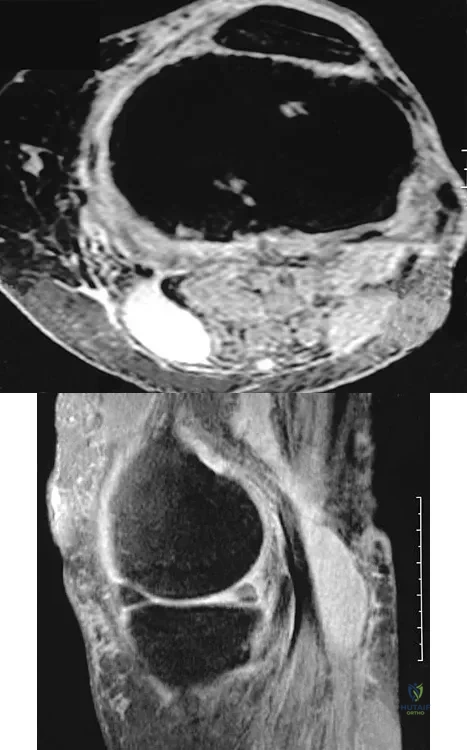

Figures 26a and 26b show the radiograph and MRI scan of a 22-year-old man with knee pain. What is the most likely diagnosis?

An 80-year-old woman notes a painless mass posterior to her left knee. MRI scans are shown in Figures 31a and 31b. What is the best course of action?